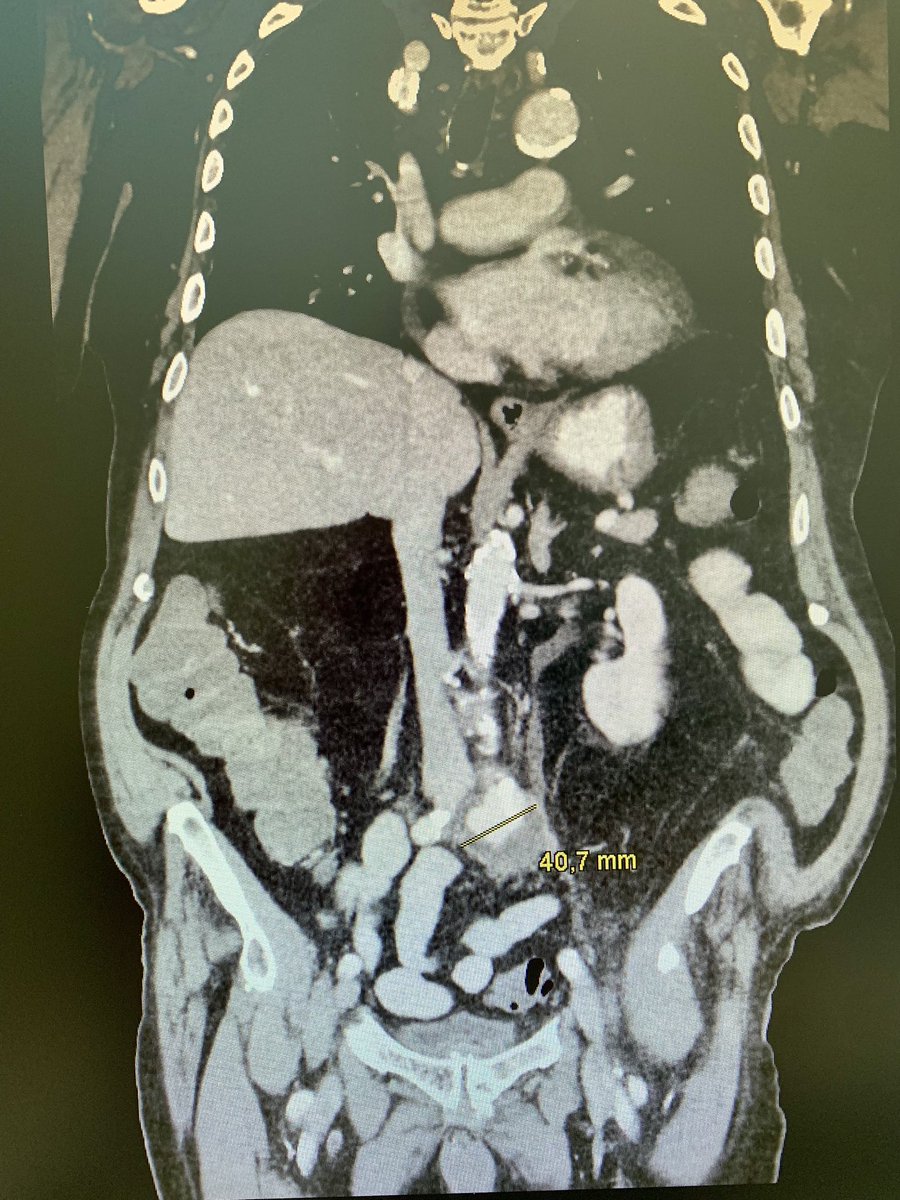

#idxposts here is 91y male patient. 7 days of a MSSA bacteremia. Current on Ampicillin/Sulbactam. BKs have cleaned up when I was first called. What do you see? How would you manage it? 😉